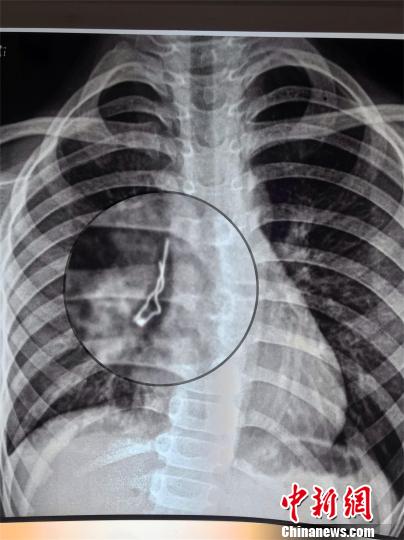

LED發光二極管卡在小路肺部右中間支氣管。院方供圖經過救治,術后第二天,小路生命體征穩定,呼吸平穩,咳嗽明顯緩解。

中新網武漢6月13日電 (周建躍 溫紅蕾 黃潔瑩)湖北咸寧7歲男孩小路(化名)咳嗽一周不見好,到醫院檢查發現有個不明金屬物體卡在肺部右中間支氣管。湖北省婦幼保健院兒內科醫生12日通過手術取出一個LED發光二極管,幸好該二極管是尖頭朝上沒有扎穿肺。

原來,小路吞下去的是個LED發光二極管,長約2.6厘米,寬7毫米。醫生介紹,這個二極管在小路肺里呆了一周,幸好鐵絲頭朝上,沒有扎穿肺。如果鐵絲朝下,隨著呼吸運動,尖頭隨時有可能刺傷氣管,引起肺部出血或者氣胸等嚴重的致死性并發癥。